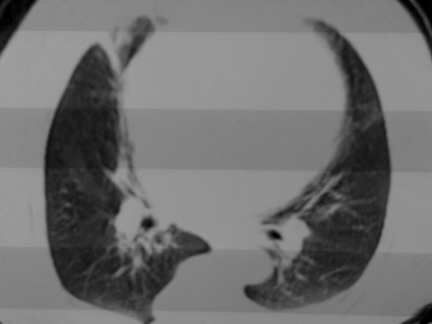

标题: CT13142:女 80 胸闷、气短、1w [打印本页]

标题: CT13142:女 80 胸闷、气短、1w

右肺炎性变,双侧甲状腺肿,胸膜肥厚。

右肺炎性变

气管,支气管软骨钙化。

右肺感染;双侧胸腔少量积液,心影增大,可能与心功不全有关;胸内甲状腺肿。

右肺炎性变,双侧甲状腺肿,胸膜肥厚,心影增大考虑心功能不全.

胸内甲状腺肿;右肺感染;双侧胸腔少量积液。

胸内甲状腺肿;右肺中叶感染;双侧胸腔少量积液;心影增大,考虑有心功能不全。